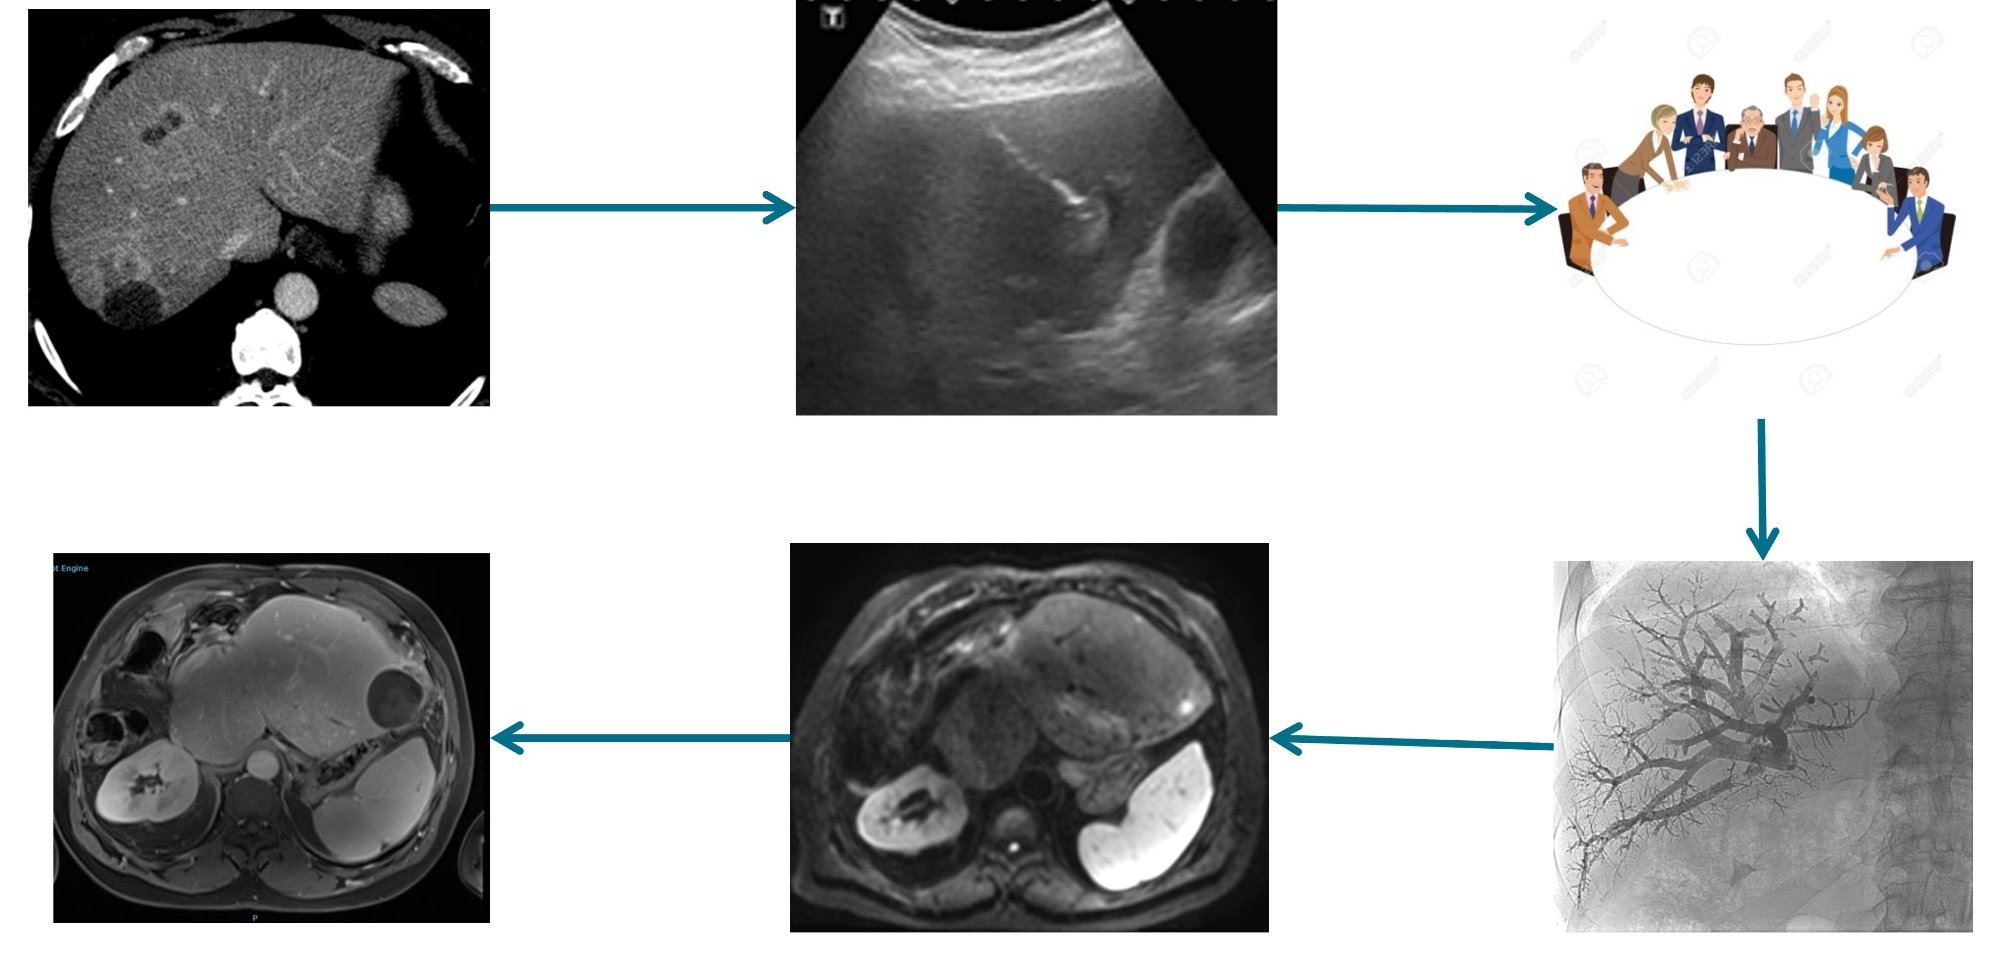

La radiologie interventionnelle est une spécialité médicale qui utilise le guidage par imagerie (scanner, IRM, échographie, fluoroscopie) pour réaliser des gestes thérapeutiques mini-invasifs sans chirurgie ouverte. Le radiologue interventionnel agit à travers la peau, via de petites ponctions, sous contrôle d'image en temps réel. Les patients rentrent souvent le jour même (ambulatoire).

Notre plateau technique comprend un bloc opératoire dédié avec salles d'angiographie, un scanner interventionnel avec arceau robotisé, et des échographes haute gamme équipés de fusion IRM/scanner/cone-beam CT pour la précision maximale.

Centre Expert Cancers du Foie

RF, micro-ondes, IRE (lésions péri-biliaires/pancréatiques), TACE, Y90, chirurgie hépatique, transplantation.

Tumeurs du foie

Micro-ondes, RF, cryoablation. IRE (NanoKnife) pour les lésions péri-biliaires.

💉Chimio-embolisation (TACE)

CHC et métastases hépatiques : traitement de référence, zéro dépassement.

☢️Radio-embolisation TheraSphere® (Y90)

Radiothérapie interne sélective par microsphères d'yttrium-90.